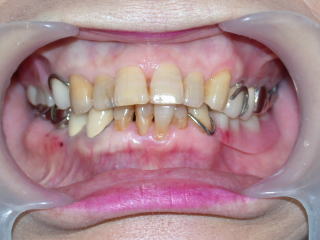

平成28年11月15日 下顎のみクラスプレスデンチャー装着しました。

薄くピタッと適合し、装着感もほとんどないとのことです。